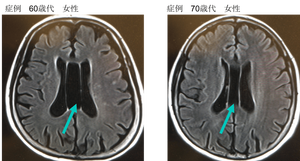

脳の中央にベルガ腔ってやつはある?

>>46

ベルガ腔ってなに

>>49

生まれつき脳室の数が多いことで透明中隔腔とも呼ばれるんだがこれがある人は糖質とかうつ病や発達障害あと痙攣なんかが多いらしい

傾向があるというだけではっきりとしたことはわかってないけど

ベルガ腔(Verga腔)とは?

人間ドックなどの主に脳MRIや頭部CTで主に指摘される正常変異に、

ベルガ腔(Verga腔)

透明中隔腔

脳室間腔(中間帆腔)

があります。

これらはいずれも脳の正中部分(真ん中の部分)に認める脳脊髄液腔の嚢胞状拡張で、合わせて正中過剰症とも呼ばれます。

いずれも乳児期に多く認めますが、加齢とともに退縮してなくなります。

ただし、正常変異として遺残することがあり、その場合は成人の頭部の画像でたまたま発見されるということです。

透明中隔腔とは、脳梁と脳弓の間の膜構造で、潜在的な空間です。

胎児では嚢胞状の構造として認めます。

通常胎生6ヶ月で閉鎖が始まり、生まれた時には、通常は消失しています。

ベルガ腔(英語では、cavum Vergae)は、その透明中隔腔が後ろ側へ進展してきたものです。

これらは通常無症状であり、病的意義がないことがほとんどですので、これらをCTやMRIの画像で認めても、指摘しないことさえあります。

指摘された場合も、よくある変異であり、ほとんど問題になることはありませんし、経過観察の必要も通常はありません。

ただし、ごく稀に症状を伴うことがあるので、症状がある場合は、過去の画像と比較することが重要です。